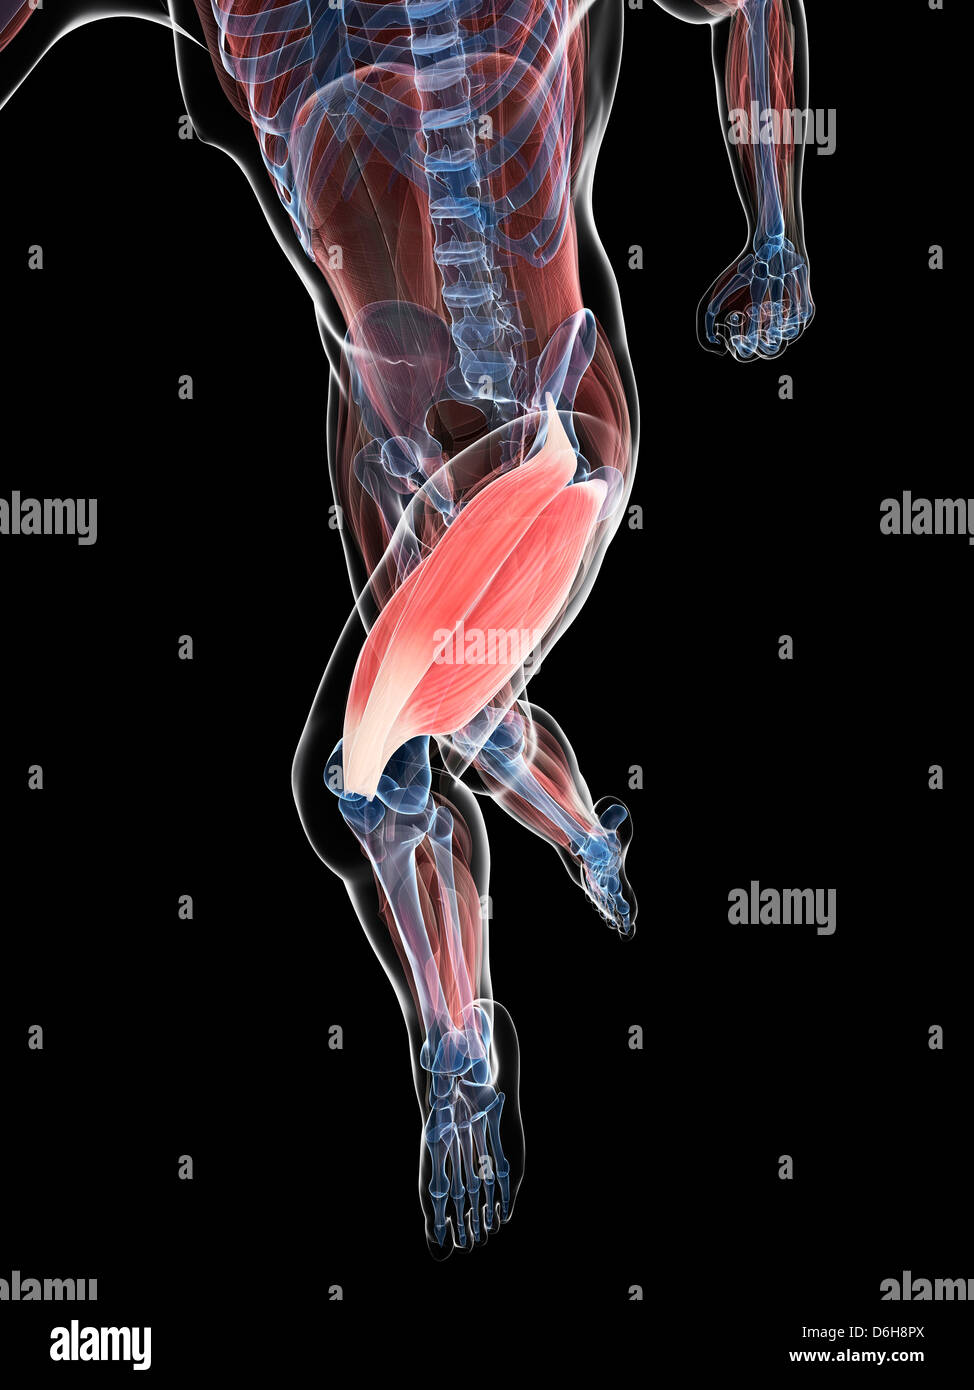

Muscle quadriceps surligné avec membre inférieur Banque D'Imageshttps://www.alamyimages.fr/image-license-details/?v=1https://www.alamyimages.fr/muscle-quadriceps-surligne-avec-membre-inferieur-image629479639.html

Muscle quadriceps surligné avec membre inférieur Banque D'Imageshttps://www.alamyimages.fr/image-license-details/?v=1https://www.alamyimages.fr/muscle-quadriceps-surligne-avec-membre-inferieur-image629479639.htmlRF2YG37KK–Muscle quadriceps surligné avec membre inférieur

La cuisse, artwork Banque D'Imageshttps://www.alamyimages.fr/image-license-details/?v=1https://www.alamyimages.fr/photo-image-la-cuisse-artwork-55699139.html

La cuisse, artwork Banque D'Imageshttps://www.alamyimages.fr/image-license-details/?v=1https://www.alamyimages.fr/photo-image-la-cuisse-artwork-55699139.htmlRFD6H8PY–La cuisse, artwork